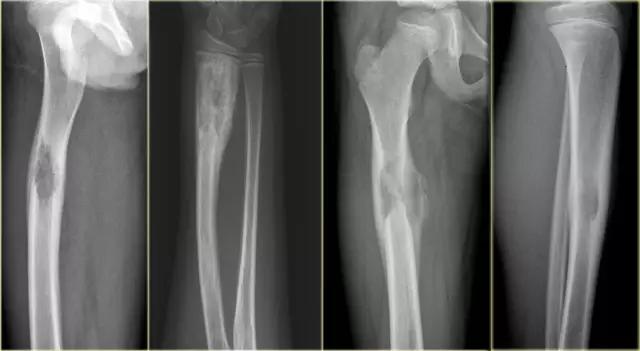

X-射线显示在腿的各个区域的典型损伤。(左)胫骨(胫骨)的病变。(中心)在膝盖附近的大腿骨(股骨)的两个损伤。(右)臀部附近的上大腿骨的大病变。